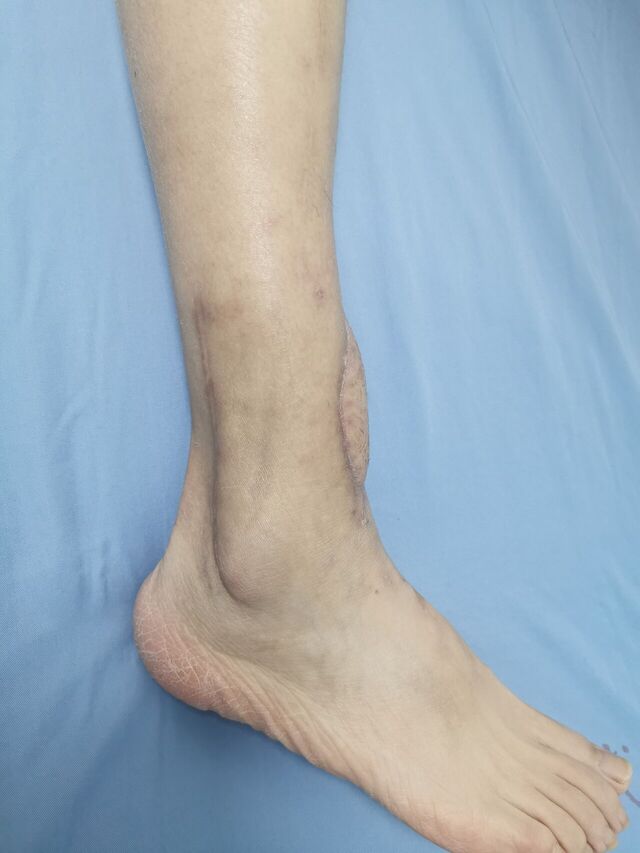

胫后动脉穿支皮瓣术后2个月